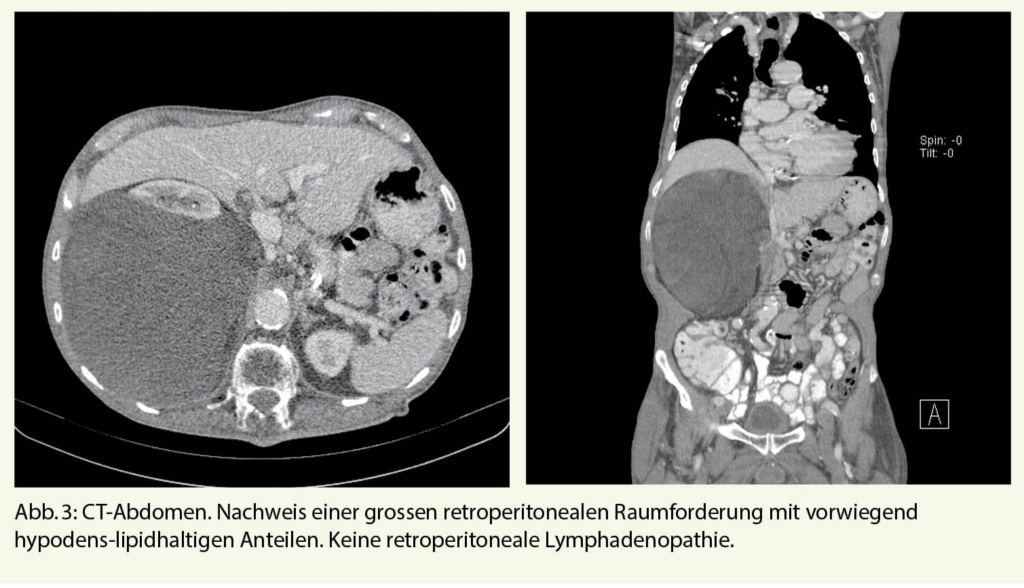

Drei Monate nach Austritt stellte sich der Patient bei seinem Hausarzt vor und beklagte rechtsseitige atemabhängige thorako-abdominale Schmerzen. Das CT Thorax/Abdomen wurde vorgezogen. Dies zeigte, neu zur Voruntersuchung, eine rechtsseitige grosse retroperitoneale Raumforderung mit vorwiegend lipomatösen Anteilen (Abb. 3). Weitere Abklärungen wie auch eine spezifische Therapie hat der Patient abgelehnt. Eine «best supportive care» Therapie mit peroraler Analgesie erfolgte mit Paracetamol und Metamizol bei Bedarf, worunter sich eine gute Schmerzkon­trolle zeigte. Der Allgemeinzustand war noch gut.

Als Risikofaktoren gelten genetische Prädisposition, Radio- oder Chemotherapie, chemische Karzinogene, chronische Irritation und Lymphödem. Das Leitsymptom ist eine schmerzfreie wachsende tumoröse Struktur. Lokale typische Tumorinvasion ist selten. Metastasierung erfolgt vor allem hämatogen und meistens in die Lunge. Als Ausnahme metastasiert das Liposarkom vom myxoiden Typ typisch in das Retroperitoneum, Abdomen, Wirbelsäule und paravertebrale Weichteilgewebe und eher selten in die Lunge.

Zum Staging wird das «Union internationale contre le cancer» (UICC) Klassifikationssystem verwendet. Das Staging muss ein Spiral-CT-Thorax enthalten. Bei myxoidem Liposarkom der Extremitäten muss zusätzlich ein Abdomen-CT durchgeführt werden. Szintigraphie, Ganzkörper MRI und PET Scan sind optional. Lymphknotenmetastasen sind selten.

High risk Patienten haben ein Rezidiv in den ersten 2 - 3 Jahren. Low risk Patienten entwickeln, wenn überhaupt, erst spät ein Rezidiv. Dem endsprechend sollten high risk Patienten in den ersten 2 - 3 Jahren alle 3 - 4 Monate mittels CT/MRI nachkontrolliert werden. Danach sollten weitere Kontrollen im 6-monatigen Intervall erfolgen. Ab dem 5. Jahr sind jährliche Kontrollen indiziert. Low Risk Patienten sollten alle 4 - 6 Monate mittels konventionellem Thoraxröntgen oder Thorax-CT in den ersten 3 - 5 Jahren nachkontrolliert werden und dann weiter jährlich. Im Gegensatz zu den anderen Sarkomen, sollen die Nachkontrollen beim myxoiden Liposarkom zusätzlich ein Abdomen-CT enthalten wegen der atypischen Metastasierung in das Retroperitoneum/Abdomen.